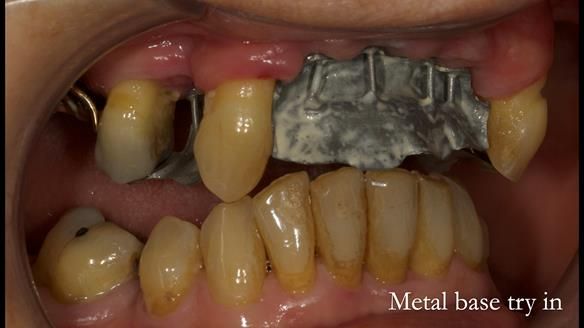

In this edition, I present the removable partial denture treatment for Jean, an 80-year-old woman with a sore mouth caused by a soft tissue-supported 'gum stripper' acrylic denture and a clenching habit. Below, I outline the step-by-step process of her treatment. It wasn't straightforward; I had to remake the denture after it fractured to achieve a satisfactory result. Each patient is unique, and sometimes a new RPD serves as a prototype. Occasionally, I need to make adjustments, learn from any mistakes, and refine the design to get it right.

The treatment has been a success over the past 4 years.